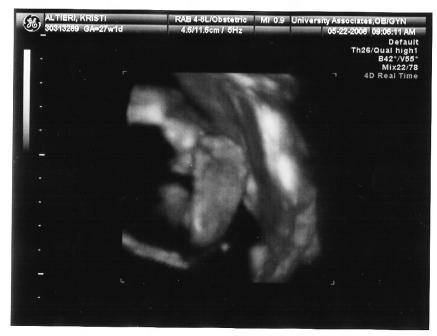

I'm back and everything went great. The cyst is barley visible and the doc said she might not need anything done after she is born. I am so happy I can't even explain. I go back in a month for another sono/check-up. I was surprised that they did a 3d sono I totally didn't expect it. She is pushing up against the placenta so there isn't a clear shot of her face.

here you go!

the first one looks great!! what a cutie. so glad all is going well.